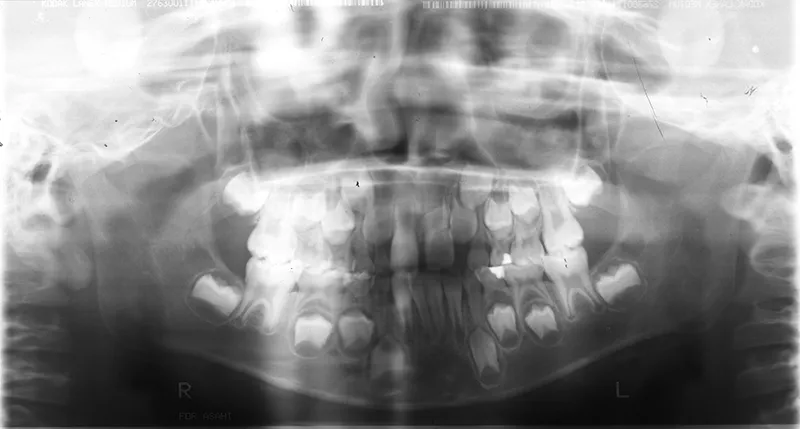

【子供の矯正(一期)】叢生・すきっ歯・永久歯が生える隙間がない・反対咬合・7歳男児【K.S様】

初診時年齢 小学校1年生 (男性) 主訴 すきっ歯・ガタガタ・受け口

診断名 叢生・反対咬合・空隙歯列 装置名

上の前歯が下の前歯より後ろに入って、受け口になっています。

下の歯は永久歯の生えるスペースがないので、オリジナル矯正装置で受け口を治して、永久歯の生えるスペースを作りました。